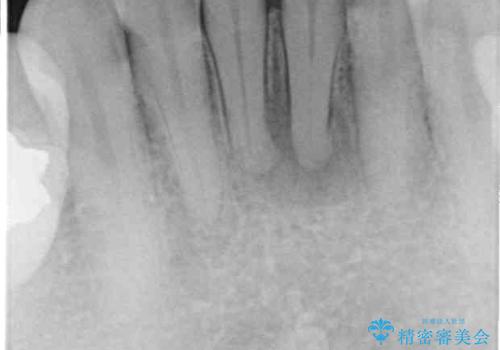

- 下顎前歯が痛んで近医を受診したところ、下顎前歯2本を抜歯してインプラント治療が必要と診断されたとのことで来院された患者様です。

診査の結果、下顎左側中切歯の神経が失活していることが痛みの原因であり、根管治療を行う必要があると診断されました。

隣在歯にも根尖部の炎症が及んでいるように見えましたが、術前診査では神経が失活している様子がなかったため、まずは原因歯から処置を行うこととしました。

初回の根管治療後には痛みが速やかに改善し、6か月後のレントゲン写真では根尖の病変が消失していることが確認できました。